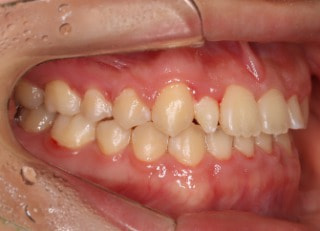

治療前